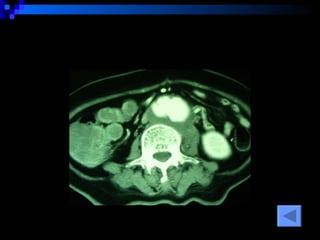

CT SCAN AAA juxtrareal -> bifurcation  Size 10*8*4 cm Inflamatory tissue  around AAA Intact renal artery Aortic dissection at juxtra renal -> bifurcation Bowel wall thickening at 3 rd -4 th  part of duodenum

CT SCAN AAAjuxtrareal -> bifurcation Size 10*8*4 cm Inflamatory tissue around AAA Intact renal artery Aortic dissection at juxtra renal -> bifurcation Bowel wall thickening at 3 rd -4 th part of duodenum